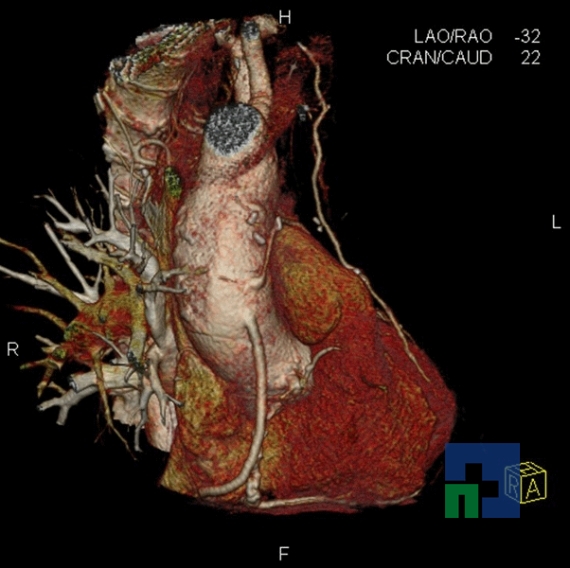

- Fistula carotido-cavernoasa